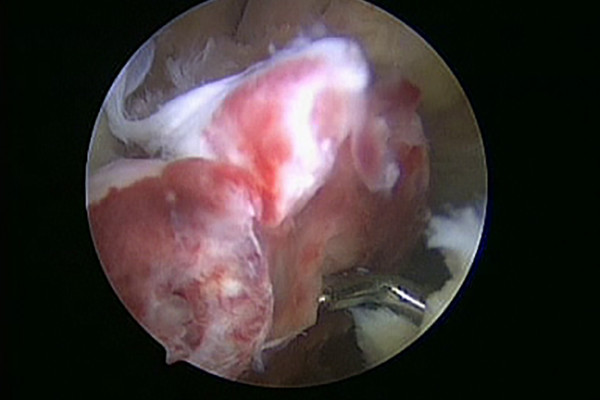

In Fällen in denen das vordere Kreuzband nur zum Teil direkt am Knochen abgerissen ist können durch eine Anmeiselung des freiliegenden Knochens Stammzellen freigesetzt und eine stabile Vernarbung erreicht werden. Diese Technik wird als „Healing Response“ bezeichnet.

Ist das Kreuzband vollständig abgerissen ist eine Heilung ohne Operation nicht möglich. Um das Kreuzband dennoch zu erhalten kommt die Ligamys® Technik oder „Dynamische Intraligamentäre Stabilisierung“ zum Einsatz. Hierbei wird das abgerissene Kreuzband über eine wenig Millimeter messende Bohrung mit Nähten wieder am Oberschenkelknochen fixiert. Um die Naht in der Zeit der Heilung zu schützen wird eine stabile Kordel als innere Schienung parallel zum Kreuzband gespannt. Diese Kordel wird im Unterschenkelknochen im eigentlichen Ligamys® Implantat verankert. Hier sorgt eine Feder dafür, dass die Kordel über das gesamte Bewegungsausmaß die selbe Spannung behält. Der gesamte Eingriff wird im Rahmen einer Kniegelenksspiegelung also ohne weite Eröffnung des Kniegelenks durchgeführt.